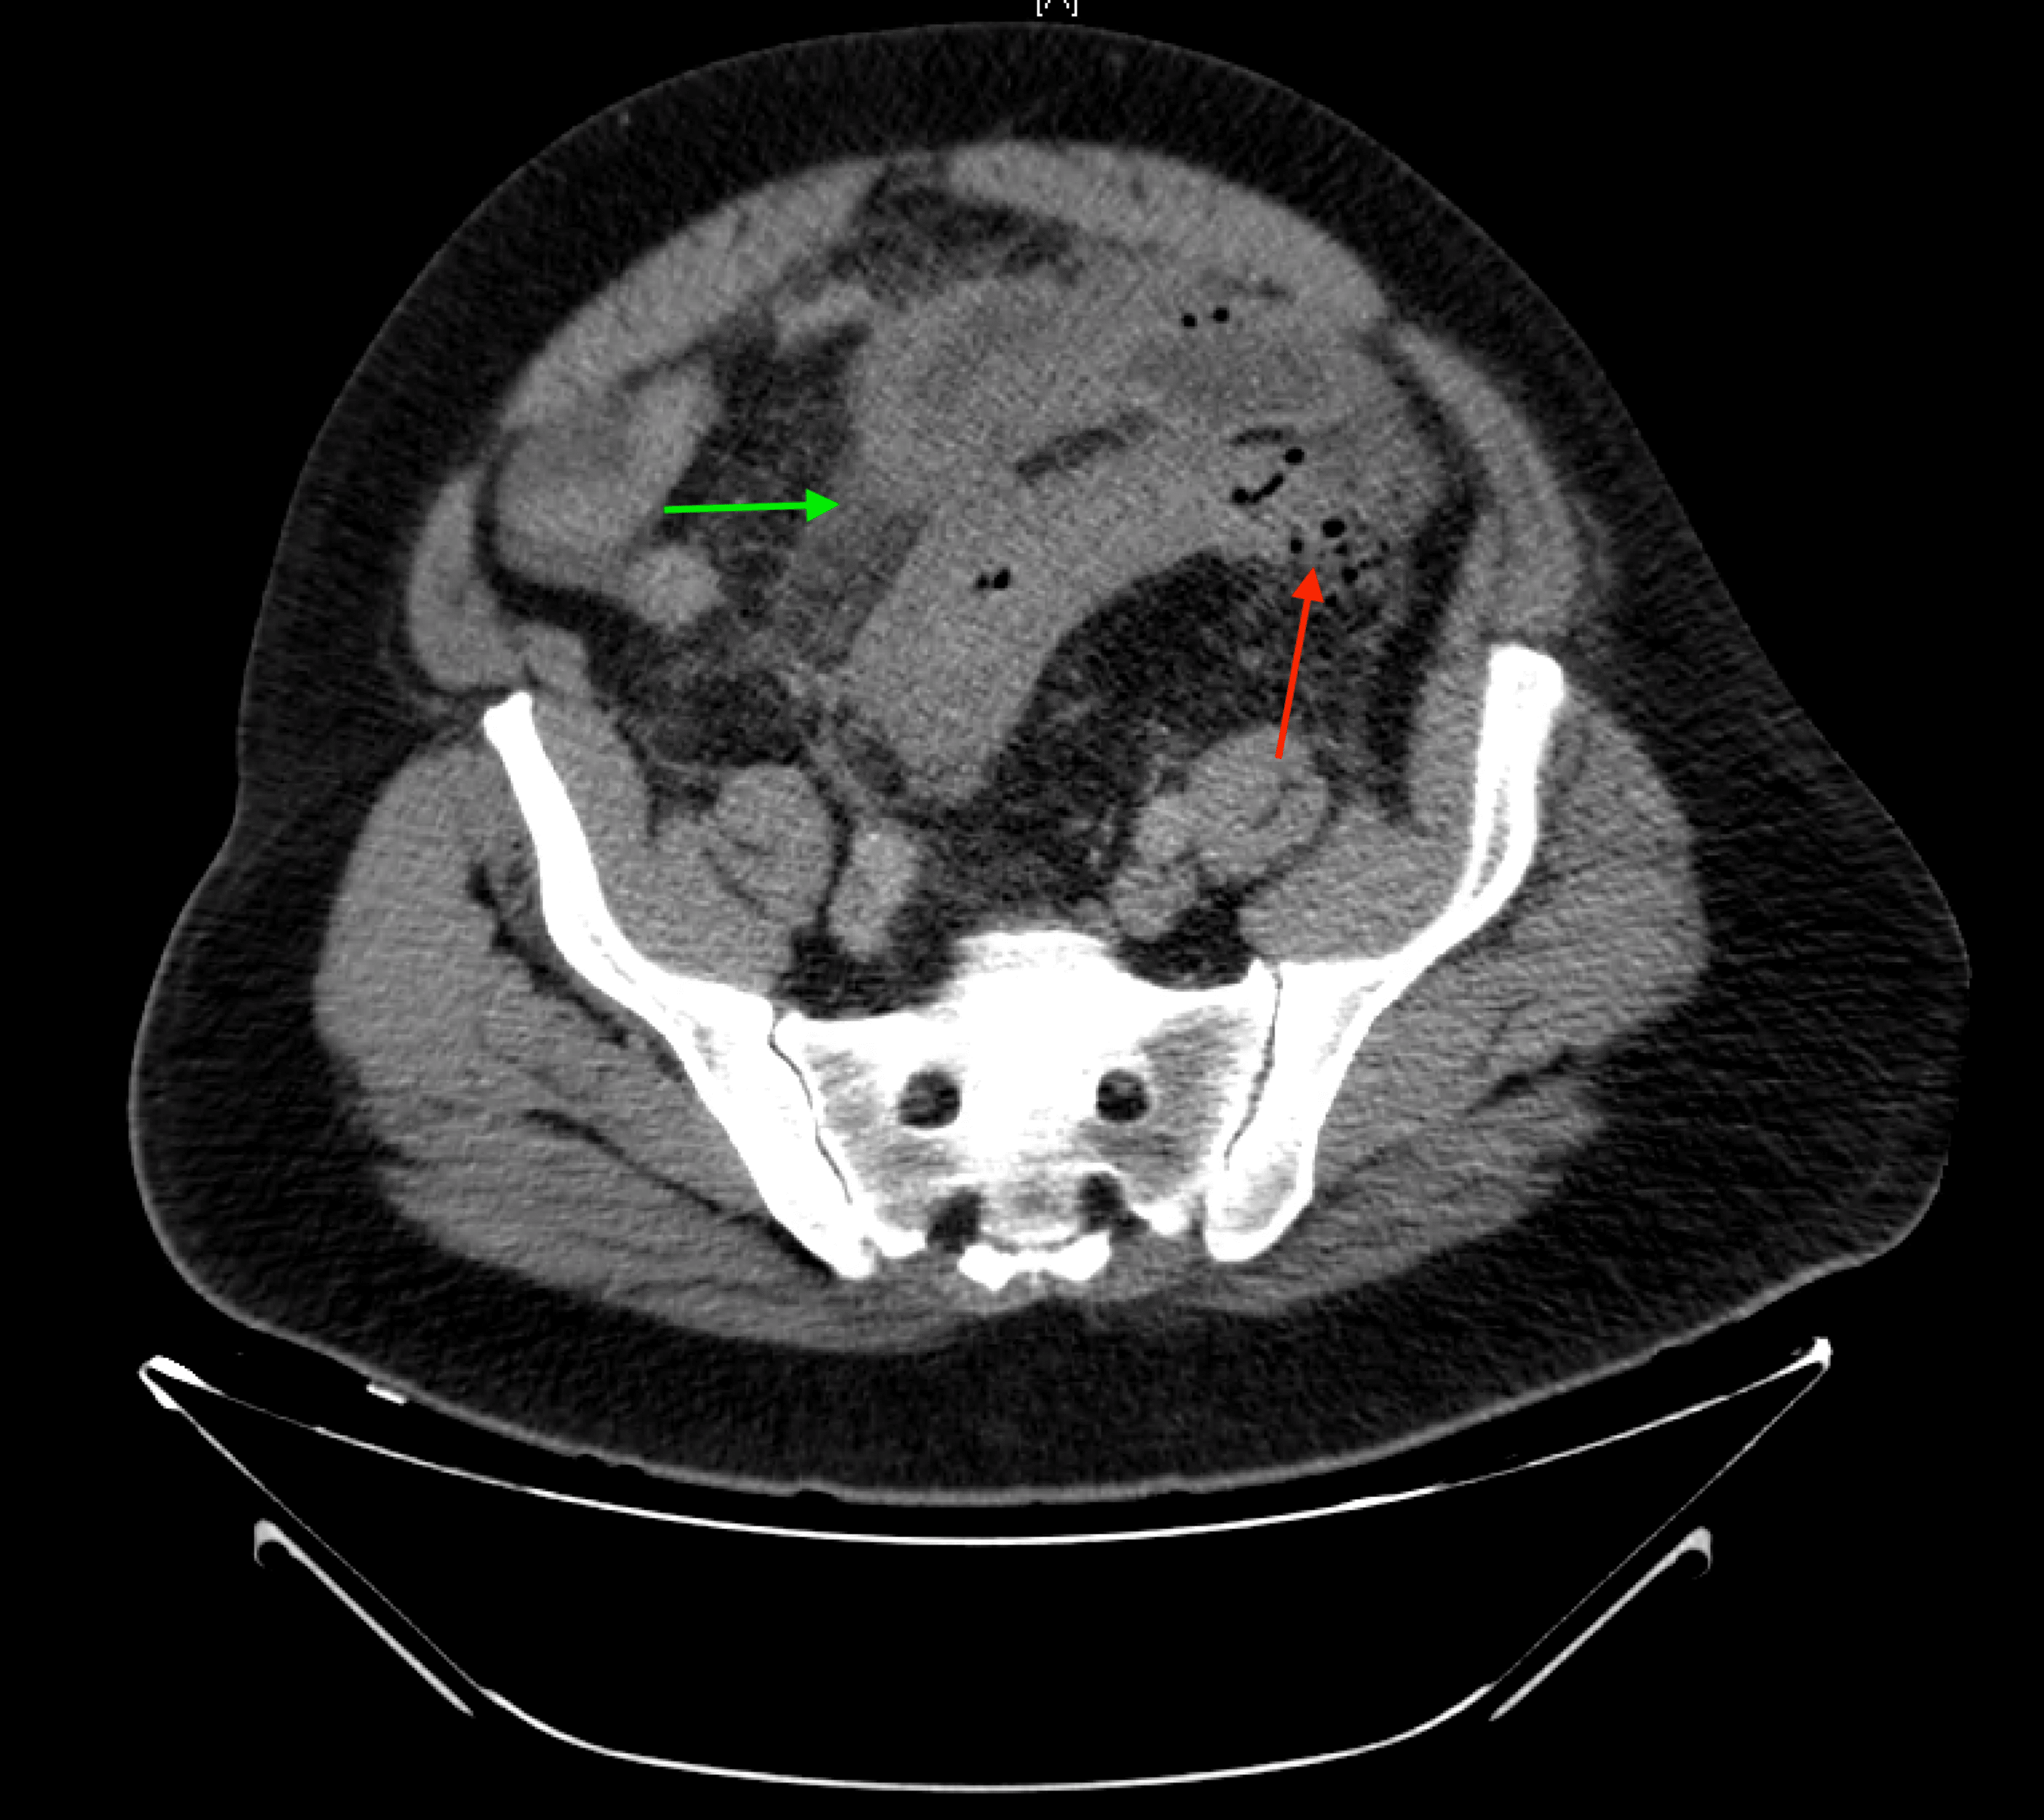

From www.ajronline.org

CT Predictors of Unfavorable Clinical of Acute Right Colonic Applesauce With Diverticulitis what you eat can help manage diverticular disease. brat is an acronym for the basic foods allowed in a brat diet: a diagnosis of diverticulitis no longer means you have a list of foods to avoid with diverticulitis. These foods are chosen because they help bind your stools. Bananas, rice, applesauce and toast. the standard american. Applesauce With Diverticulitis.